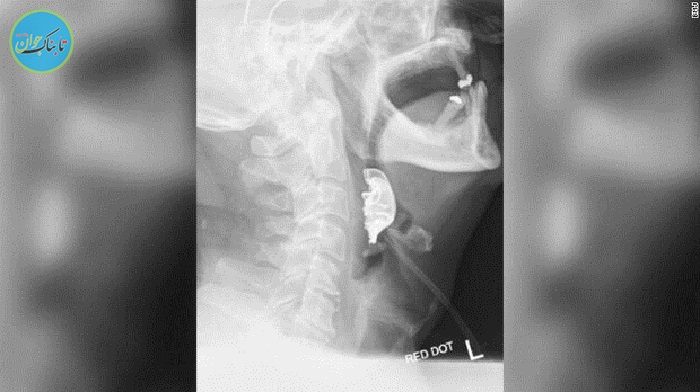

سرانجام پس از عکس برداری مشخص شد یک جسم نیم دایرهای روی تارهای صوتی او قرار دارد، که باعث ایجاد تاول و تورم داخلی شده است.

این مرد ۷۲ ساله گفته بود هنگام مراجعه به بیمارستان، دندانهای مصنوعی خود را از دست داده است. با این حال پس از تشخیص این ماجرا وی برای خارج کردن دندانهای مصنوعی خود بار دیگر راهی اتاق جراحی شد.